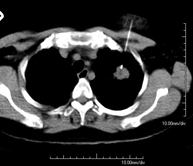

- TC Tórax

Prueba diagnóstica que consiste en obtener imágenes del tórax de alta definición anatómica (pulmones, corazón, mediastino, grandes vasos, caja torácica, etc.) mediante el empleo de un equipo de TC (Tomografía Computarizada). Dichas imágenes se estudian posteriormente en una estación de trabajo que permite reconstrucciones bidimendionales en diferentes planos del espacio y también reconstrucciones 3D (volumétricas). Algunos estudios requieren el empleo de contraste yodado para mejorar la definición de las imágenes.